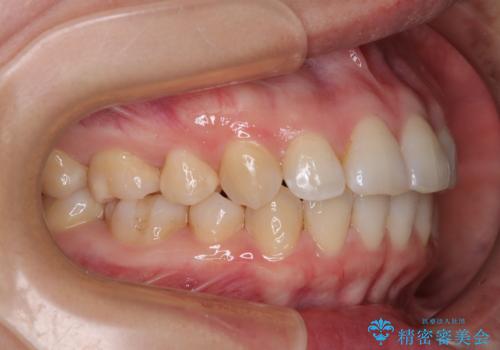

- 上下前歯の後戻りを気にして来院された患者様です。

インビザラインでの治療を希望されていて、デコボコの程度が中等度であり、安価なパッケージにて対応可能と判断されたため、インビザライン・モデレートを用いて矯正治療を行うこととしました。